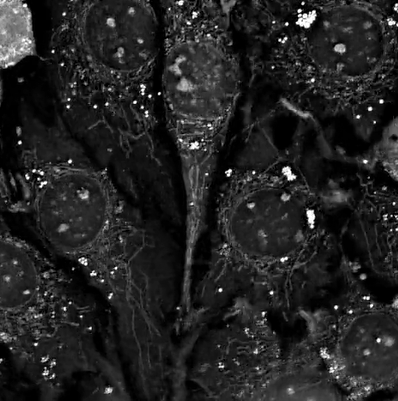

NanoLive 的全息斷層掃描技術是一種結合全息術和斷層掃描原理的新型成像技術。它利用物體對光的折射率差異 (Refractive Index Difference),從多個角度獲取全息影像 (Holographic Images),然後利用計算機重建出物體的三維 (3D) 折射率分佈圖 (RI Tomogram)。

NanoLive 的 3D Cell Explorer 使用低功率雷射 (Low-power Laser, 520 nm, 0.1 mW),從多個角度照射樣本,測量穿過細胞的光波的相位延遲 (Phase Delay)。由於細胞內不同結構,例如細胞核、細胞質、細胞膜等,具有不同的折射率 (RI),因此光波在穿過這些結構時會產生不同的相位延遲。

• 內源性對比 (Intrinsic Contrast):細胞內的各種結構 (例如細胞核、細胞質 、細胞膜 、細胞器 等) 具有不同的折射率 (RI),這使得全息斷層掃描無需染色即可區分這些結構。通過測量細胞內各區域的折射率分佈 (RI Distribution),可以了解細胞的組成和結構。

• 動態追蹤 (Dynamic Tracking):由於全息斷層掃描可以快速地獲取細胞的三維 (3D) 折射率分佈 (RI Distribution),因此可以實時追蹤細胞內部的動態變化 (Dynamic Changes),例如細胞器的運動 (Organelle Movement)、物質的運輸 (Material Transport)、細胞的形變 (Cell Deformation) 等。

• 細胞結構與功能研究 (Cell Structure and Function Study):觀察細胞內部的精細結構 (Subcellular Structures),例如細胞核 (Nucleus)、細胞器 (Organelles)、細胞骨架 (Cytoskeleton) 等,研究它們的結構與功能之間的關係 (Relationship)。